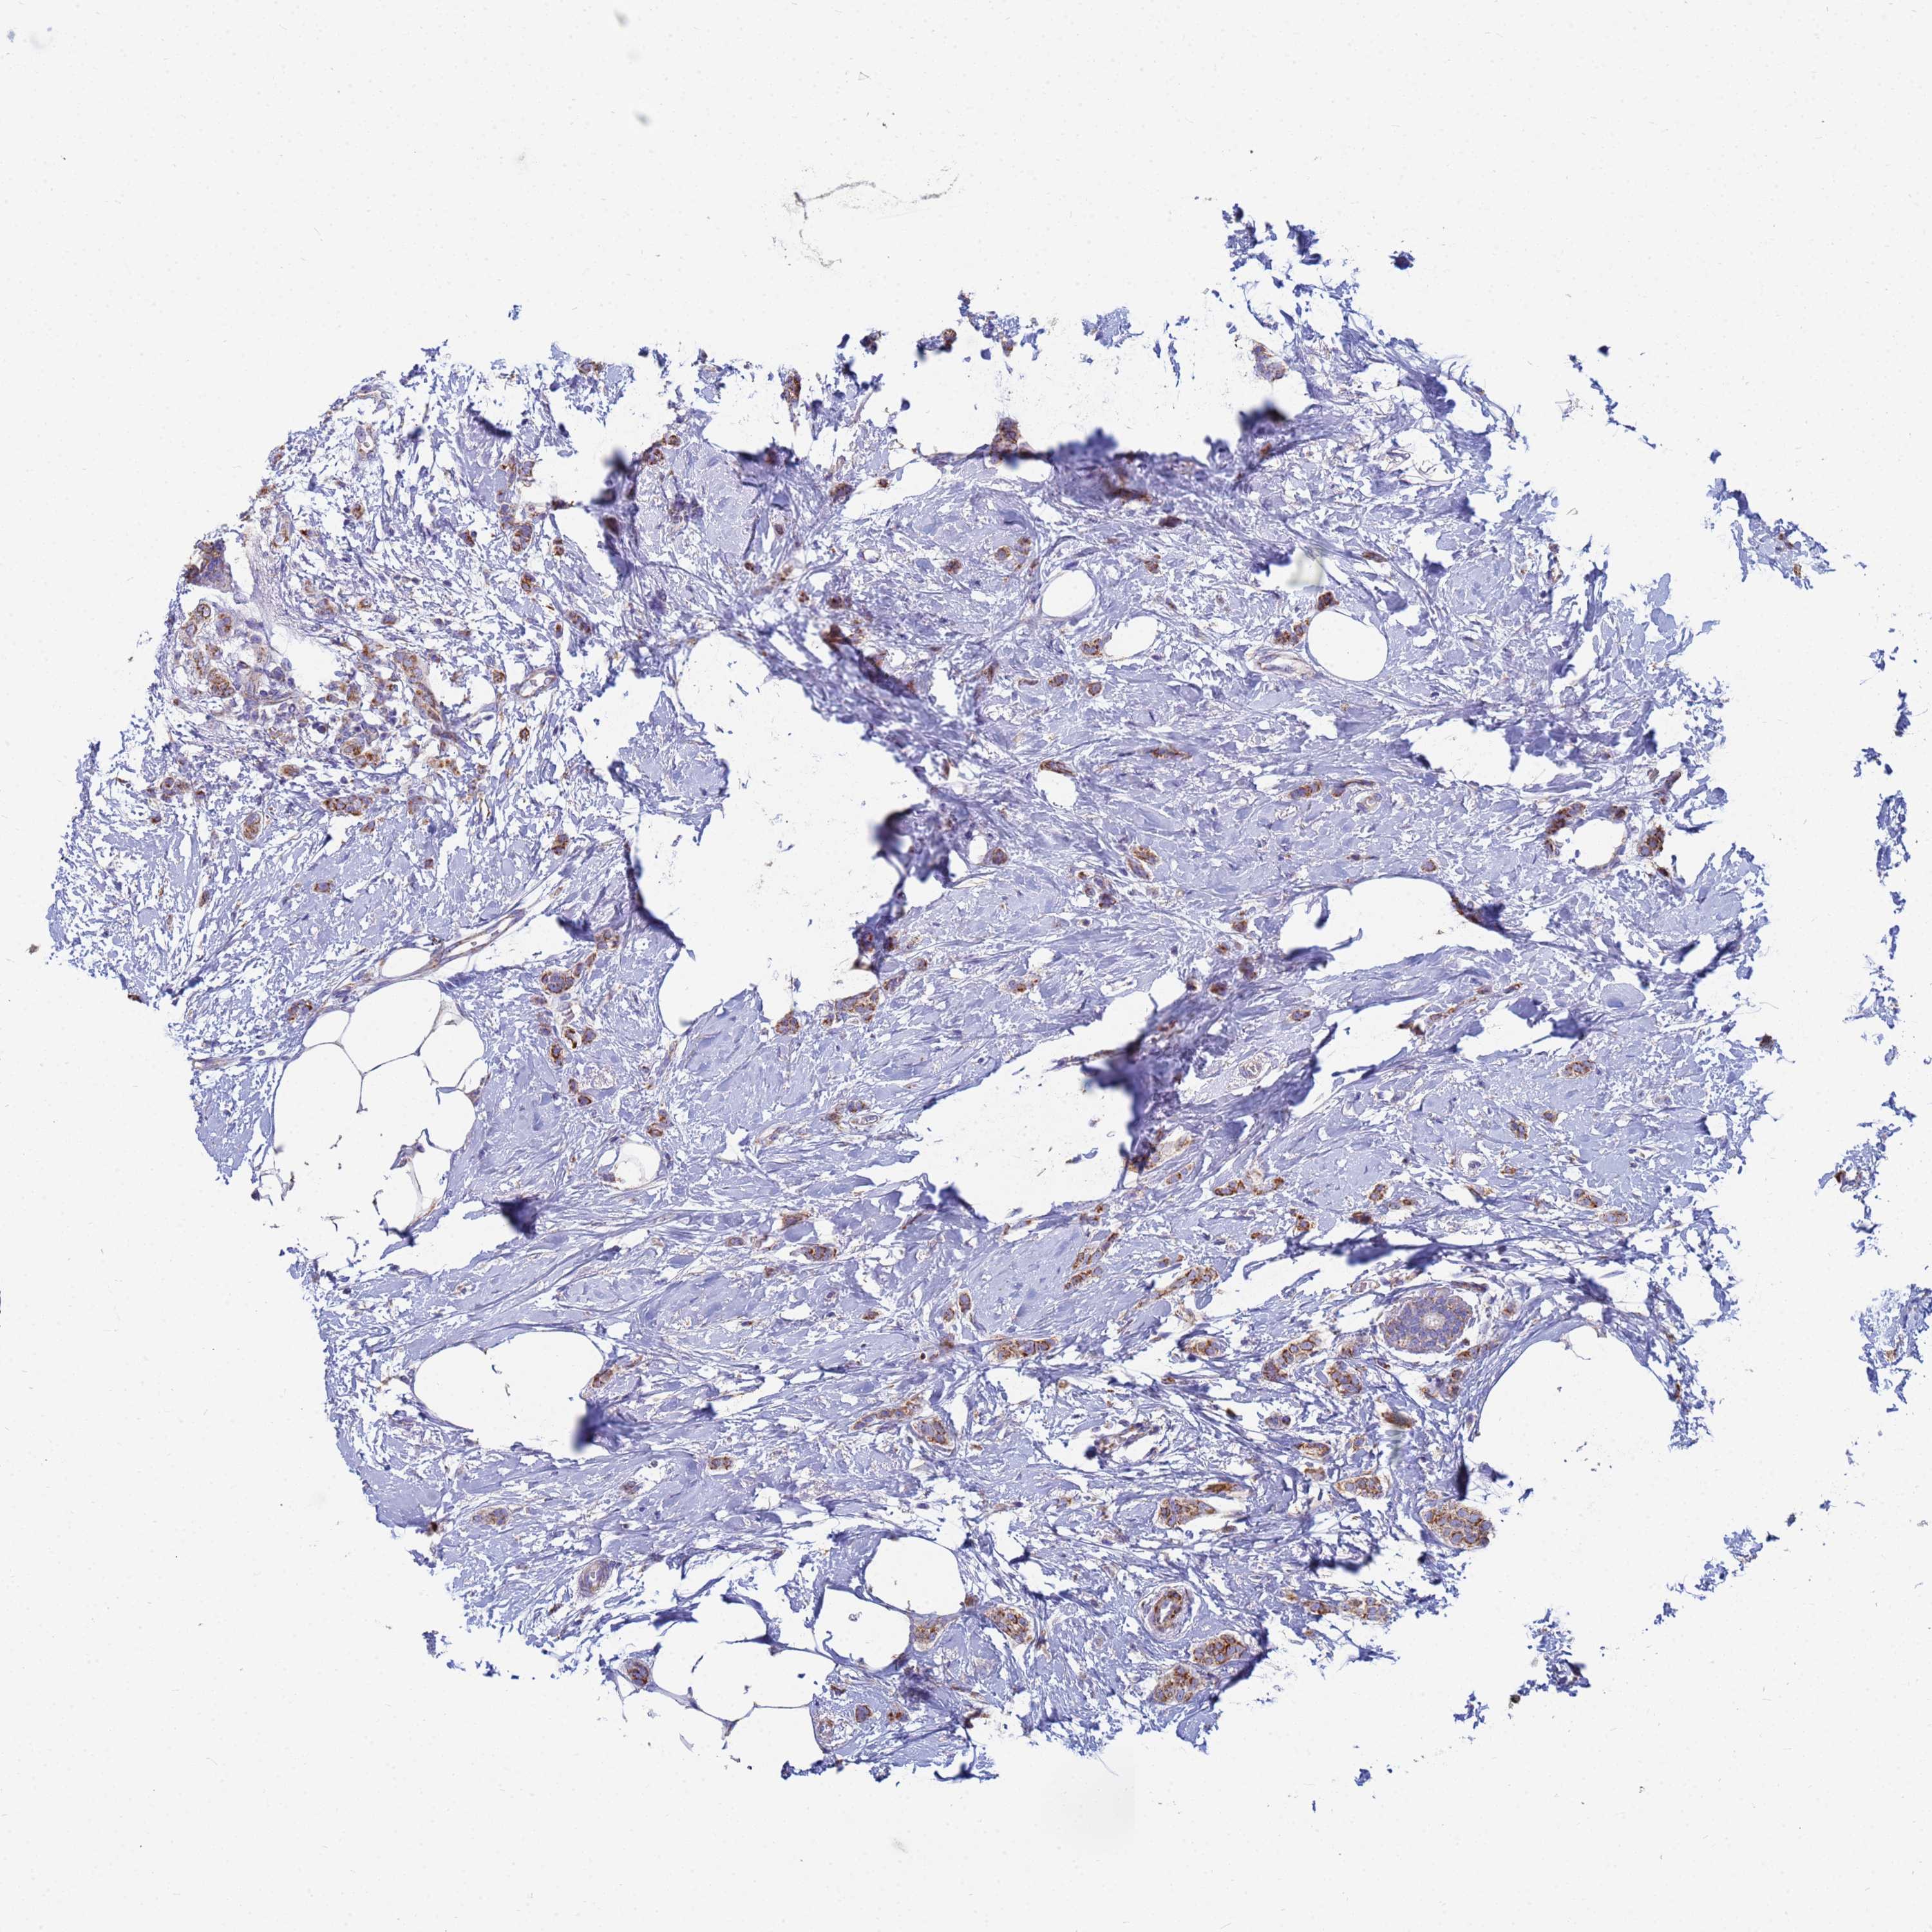

CANCER BREAST CANCER Show tissue menu

BRCA TCGA BRCA VALIDATION PROTEIN EXPRESSION

ANTIBODIES

AND

VALIDATION